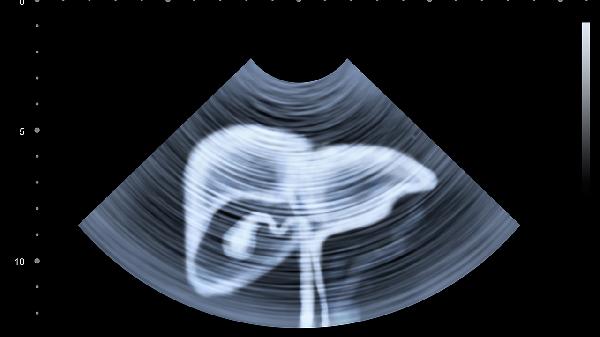

超声和甲胎蛋白检测是筛查肝癌的重要手段,高危人群建议每半年检查一次。